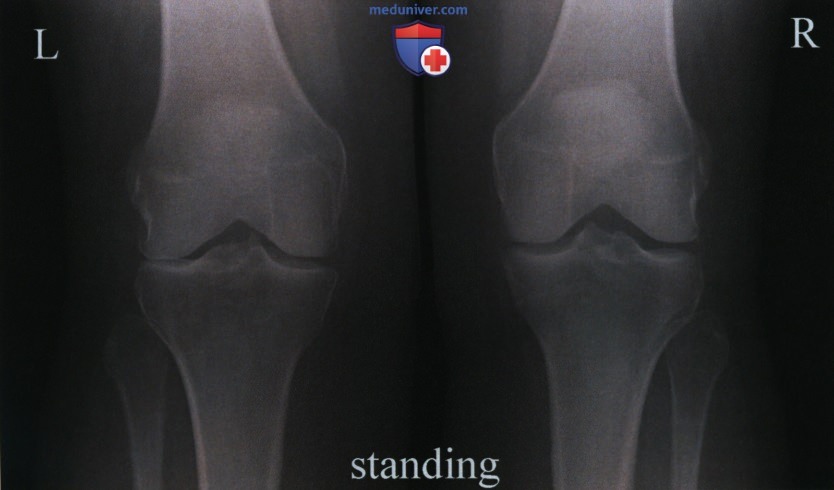

Медицинские снимки: рентген коленного сустава при остеопорозе